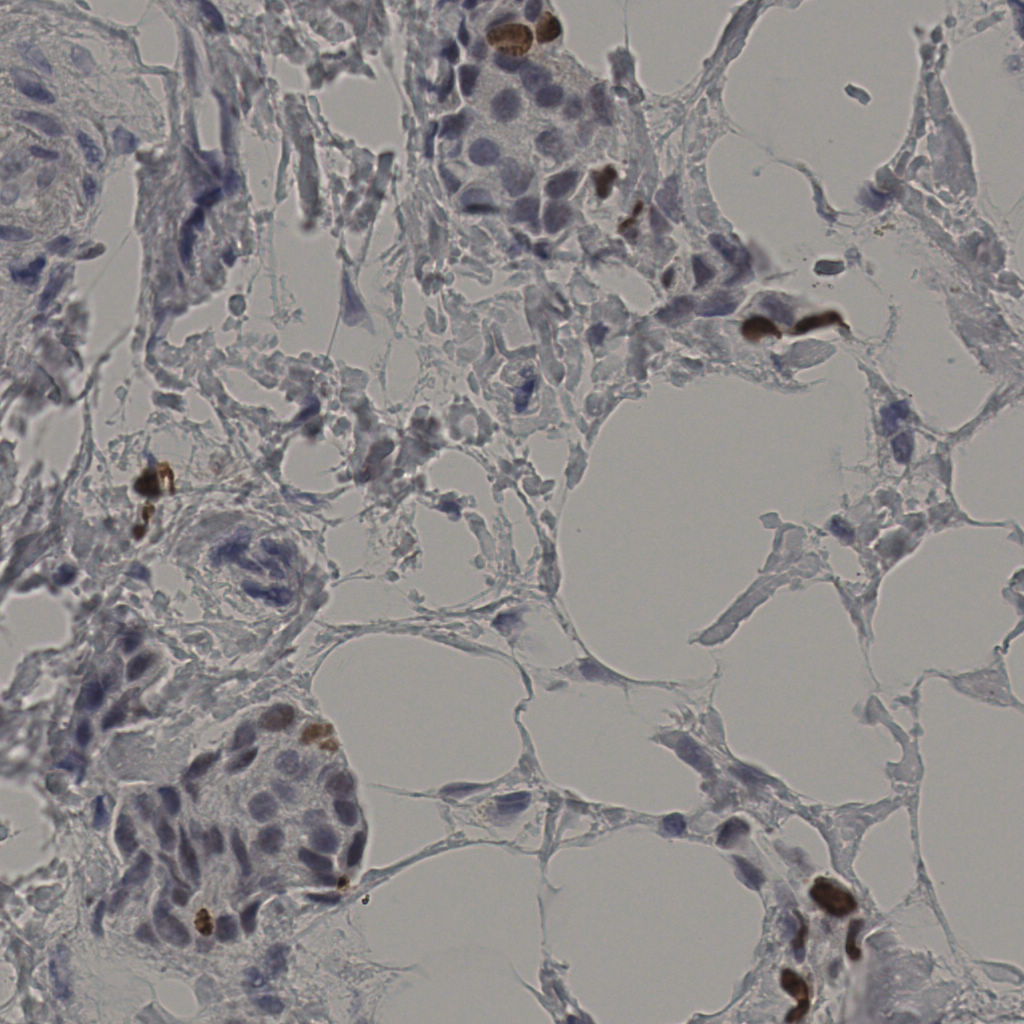

slice_38_11_x34048_y9856.png

slice_38_11_x3404...